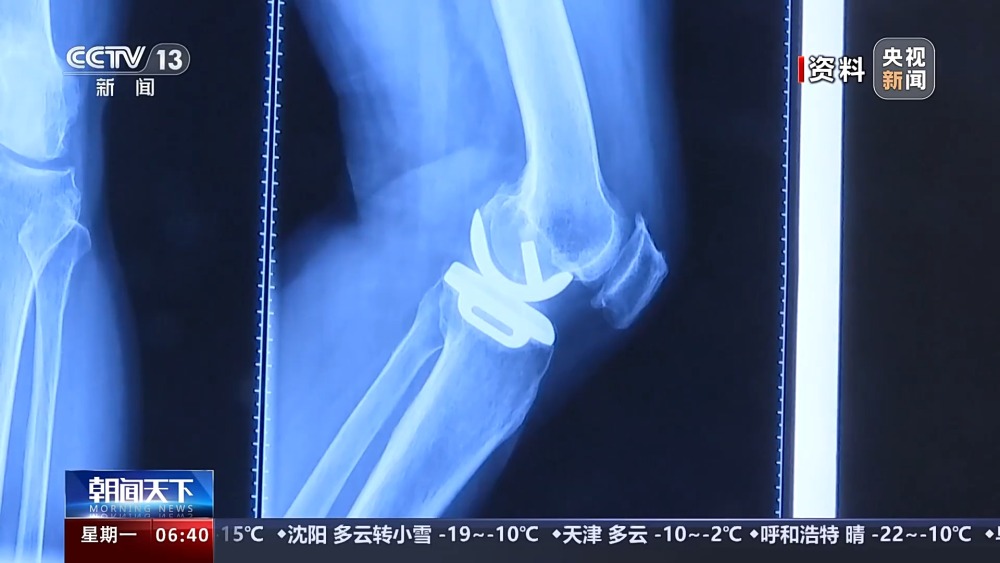

目前,我國有超過1億人患有骨關(guān)節(jié)炎,65歲以上人群中,骨關(guān)節(jié)炎發(fā)病率接近50%。以前,嚴(yán)重骨關(guān)節(jié)炎患者主要通過膝關(guān)節(jié)置換手術(shù)來維持行走等基本功能。膝關(guān)節(jié)置換手術(shù)存在術(shù)后關(guān)節(jié)僵硬、長期疼痛等問題。保膝治療包括藥物、理療等保守治療,以及手術(shù)治療。

保膝手術(shù)主要包括截骨術(shù)和單髁置換術(shù),其中截骨術(shù)在解決患者疼痛癥狀的同時,阻止下肢異常應(yīng)力對膝關(guān)節(jié)的進(jìn)一步損傷,膝關(guān)節(jié)內(nèi)所有軟骨韌帶、半月板都得到了保留。內(nèi)側(cè)單髁置換術(shù),使膝關(guān)節(jié)外側(cè)健康的軟骨和半月板得到了保留,膝關(guān)節(jié)內(nèi)外側(cè)的韌帶維持原有狀態(tài),患者康復(fù)后,擁有正常的膝關(guān)節(jié)功能。